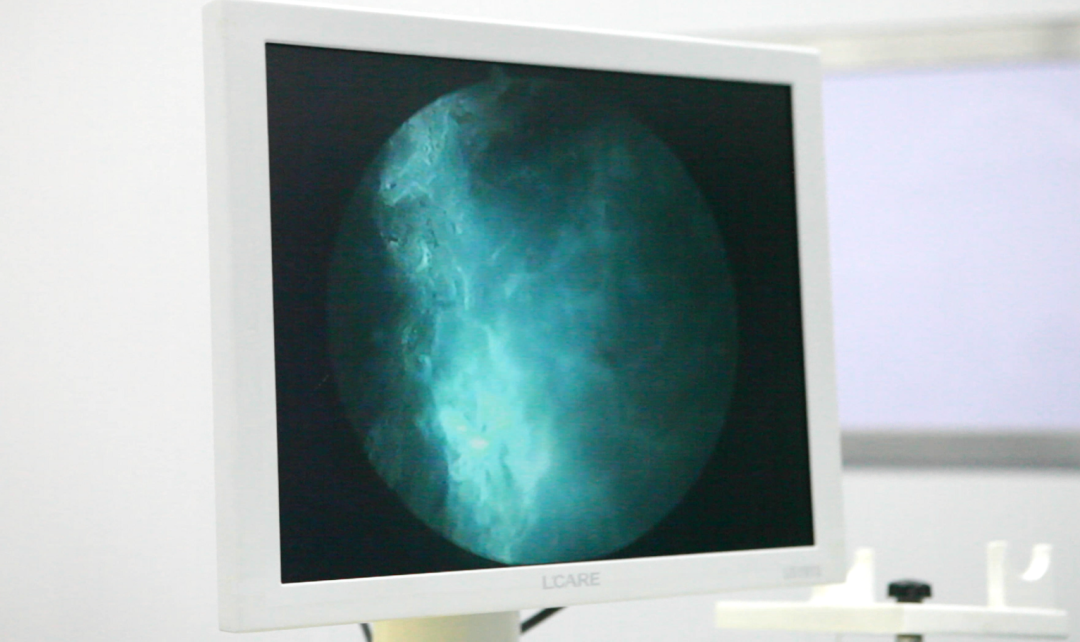

泌尿外科团队为王先生完成了蓝激光前列腺增生汽化术,手术非常顺利,术中几乎无出血。术后王先生恢复良好,排尿通畅,目前已治愈出院。

陕西冶金医院超微创蓝激光汽化术:损伤小、手术时间短、出血少、安全性高、恢复快、适用广泛,在性功能保护方面表现出色。增生腺体不太大的患者,手术过程仅十几分钟。较大的增生腺体,手术过程20多分钟。陕西冶金医院已有众多前列腺增生患者得到蓝激光新技术治疗,最大年龄90岁,最小年龄51岁,均取得良好效果。